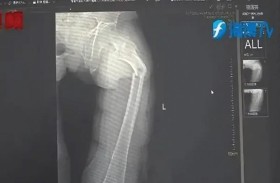

عطس فكسر عظام فخذه

تسبّبت نوبة سعال حادة في كسر فخذ صيني، في حالة نادرة صدمت الأطباء بعد وصوله إلى قسم الطوارئ في مقاطعة فوجيان الصينية. وفي البداية، ظن  "يي" 35 عاماً، أن الآلام الحادة في ... إقرأ المزيد